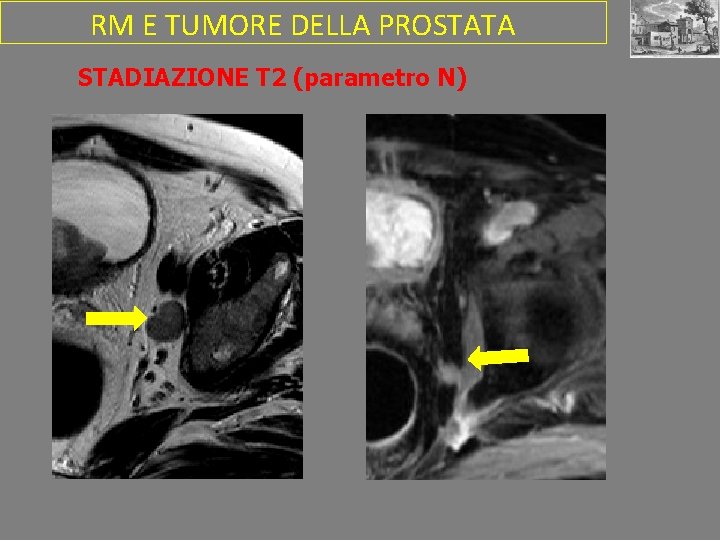

RM E TUMORE DELLA PROSTATA STADIAZIONE T 2 (parametro N)